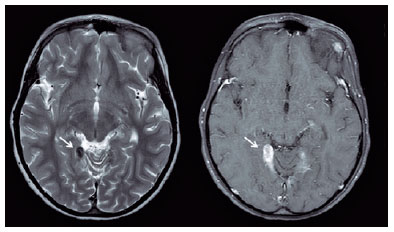

Two weeks after the initial examination, the child presented tonic-clonic seizures, disorientation, and confused speech. On physical examination, he was eupneic, afebrile, hydrated, and had no lymph node enlargement. Neurological examination revealed no meningeal or focal signs. Seizure treatment was started with phenobarbital administration. Electroencephalography revealed no abnormalities. Head computed tomography revealed findings suggestive of calcification. Cerebrospinal fluid analysis revealed normal pressure and appearance, with normal chloride and protein levels, low glucose level (50 mg/dl; normal range, 60-80 mg/dl), and high lactic dehydrogenase level (36 U/l; normal range, <24 U/l). From, the global and specific cytology analyses, the following values were obtained: leukocytes, 4/mm3 and erythrocytes, 11/mm3. Head magnetic resonance imaging (MRI) revealed bilateral meningeal nodular thickening with homogeneous enhancements in the cerebellar tentorium and axial T2, of approximately 2.6 × 1.0 cm, with features of CNS tuberculoma (Figure 2).

01-fig02.jpg)

In children, CNS tuberculoma usually presents with increased intracranial tension, seizures, and localizing neurological signs. The disease may also present with have prolonged low-grade fever with or without vague behavioral disturbances or even remain silent for many months. Childhood tuberculomas can occur in the brain (parenchymal) but often originate from meninges or even ependyma (meningeal), adjacent to the dense basal meningovascular enhancement. MRI is the modality of choice for the assessment of potential tuberculomas, which show solid caseous necrosis centrally(9).

PPD response gauges the reaction to tuberculin. In general, a response of >10 mm is considered positive. In populations vaccinated with BCG, PPD response may be difficult to interpret. In general, indurations >15 mm are more related to infection with TB bacillus than to skin hypersensitivity caused by the vaccine(10). In this case, the tuberculoma diagnosis was presumed on the basis of the PPD reading and MRI features.